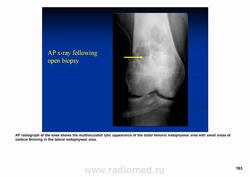

(A) Рентгенография, показывающая большие литические поражения (стрелки)